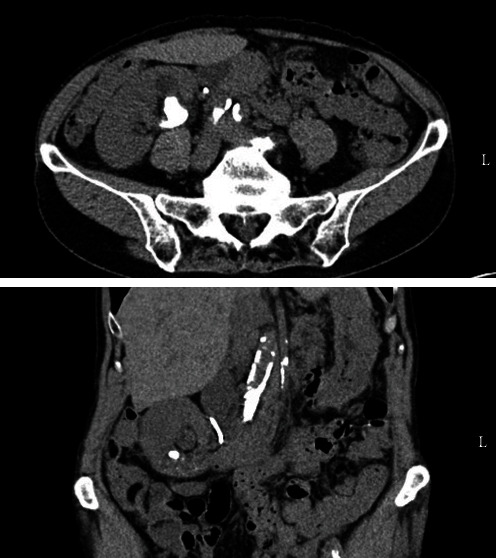

鹿角状结石给泌尿外科带来了挑战,通常需要采用经皮肾镜碎石术(PCNL)等侵入性更强的手术,以较少的手术次数清除大块结石。我们在此介绍一例 76 岁女性患者的病例,她患有慢性肾病和右肾盂旋转不良,因 3.5 厘米的鹿角状结石接受了 PCNL 手术。术后,她出现了罕见的升结肠穿孔并发症,需要紧急手术干预,包括剖腹探查术和右半结肠切除术。PCNL 期间发生结肠穿孔的情况非常罕见(0.3%-0.8%)。术前成像,即腹部和盆腔计算机断层扫描(CT),对于识别解剖变异和降低损伤风险至关重要。保守治疗策略在类似病例中取得了成功,这强调了及时识别和多学科治疗的重要性。该病例为有关这种罕见并发症的文献匮乏做出了贡献,强调了详细的术前规划对避免 PCNL 并发症的必要性,尤其是对肾脏解剖结构复杂的患者。未来的研究应侧重于为解剖异常的患者制定量身定制的 PCNL 指南,以提高手术安全性并优化治疗效果。

Staghorn calculi pose challenges in urology, often necessitating more invasive procedures such as percutaneous nephrolithotomy (PCNL) to clear a large stone burden with fewer procedures. Here we present a case of a 76-year-old female with chronic kidney disease and a malrotated right pelvic kidney who underwent PCNL for a 3.5 cm staghorn calculus. Postoperatively, she developed a rare complication of ascending colon perforation, requiring emergent surgical intervention including exploratory laparotomy and right hemicolectomy. Colon perforation during PCNL is rare (0.3%-0.8%). Preoperative imaging, namely computed tomography (CT) of the abdomen and pelvis, is crucial to identify anatomical variations and mitigate the risk of injury. Conservative management strategies have demonstrated success in similar cases, emphasizing the importance of prompt recognition and multidisciplinary management. This case contributes to the paucity of literature regarding this rare complication underscoring the necessity for detailed preoperative planning to avoid complications in PCNL, especially in patients with complex renal anatomy. Future research should focus on developing tailored guidelines for PCNL in patients with anatomical abnormalities to enhance procedural safety and optimize outcomes.